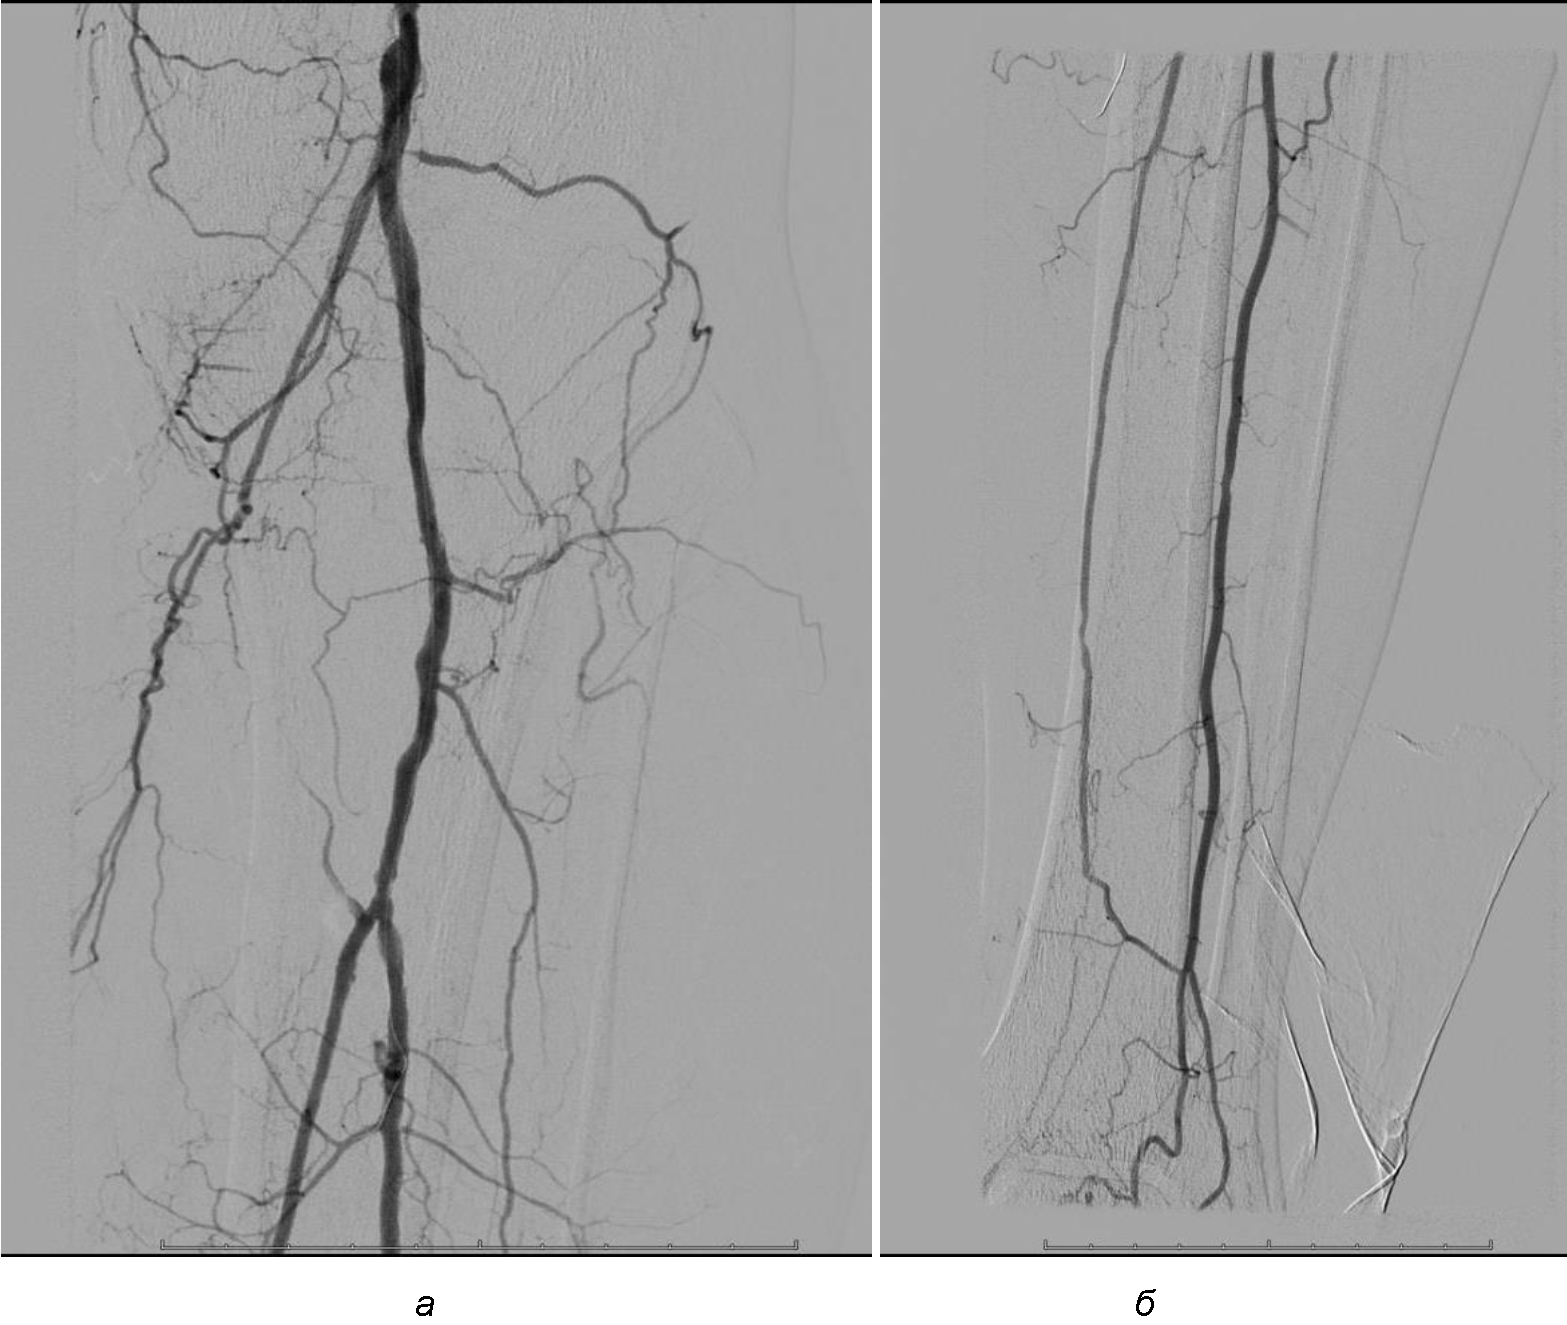

Операция. Транслюминальная баллонная ангиопластика (ТЛБАП) подколенной артерии, тибиоперонеального ствола слева. Под м/а выполнена пункция левой бедренной артерии, установлен интродьюсер 6 Fr. Выполнена селективная ангиграфия артерий левой нижней конечности при которой выявлена субокклюзия подколенной артерии и окклюзия тибиоперонеального ствола (рис. 1). Выполнена ТЛБАП в зоне субокклюзии баллоном 5,0 × 40 мм, давление 8 атм. В области тибиоперонеального ствола ТДБАП баллоном 3,0 мм × 100 мм, давление 10 атм. Получен хороший антеградный кровоток в подколенной, заднебольшеберцовой и малоберцовой артериях (рис. 2). Передняя большеберцовая артерия окклюзирована.

Рис. 1. Ангиограмма больной М. до ангиопластики. Стеноз подколенной артерии (прерывистая стрелка). Окклюзия артерий голени (сплошная стрелка)